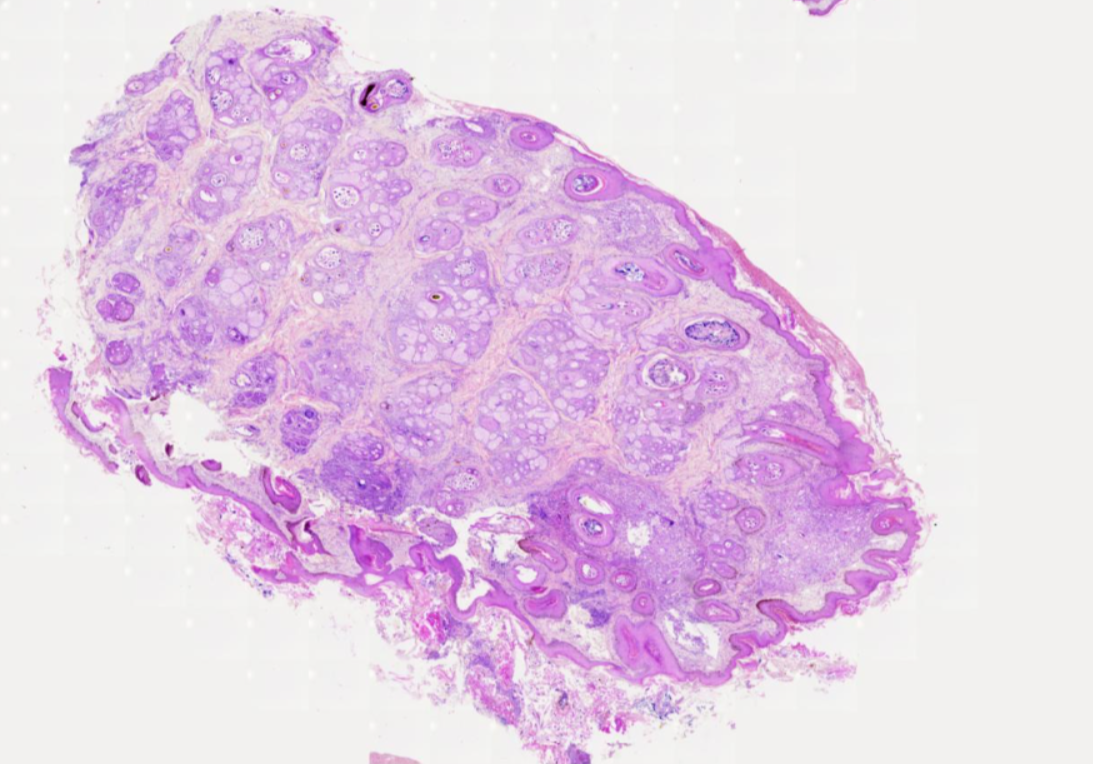

PROTOZOOS

HELMINTOS

ECTOPARÁSITOS